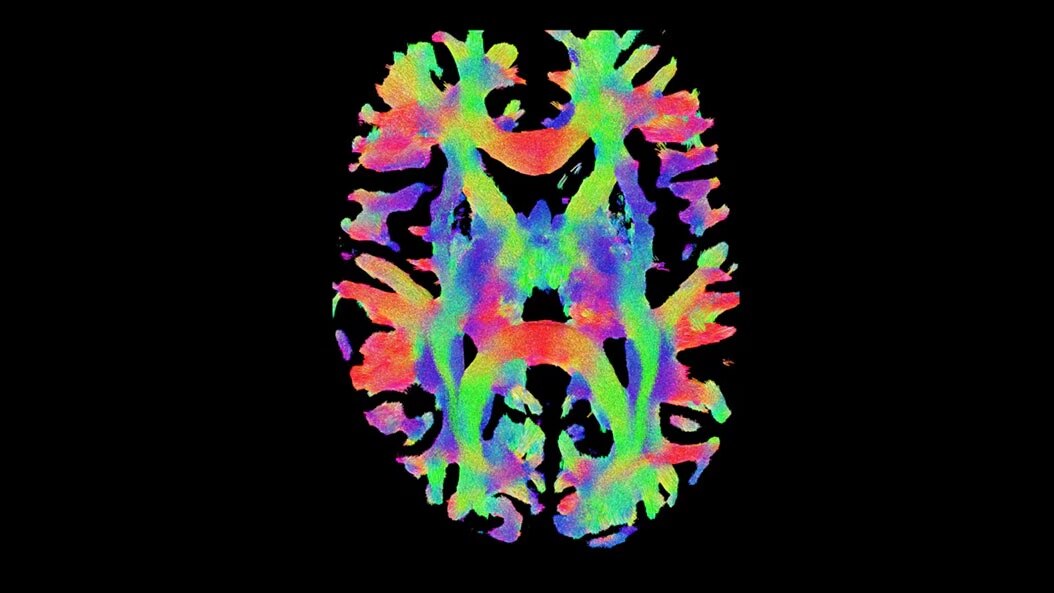

Concussion & mTBI imaging

Advanced quantitative MR imaging can detect structural and functional neurological changes